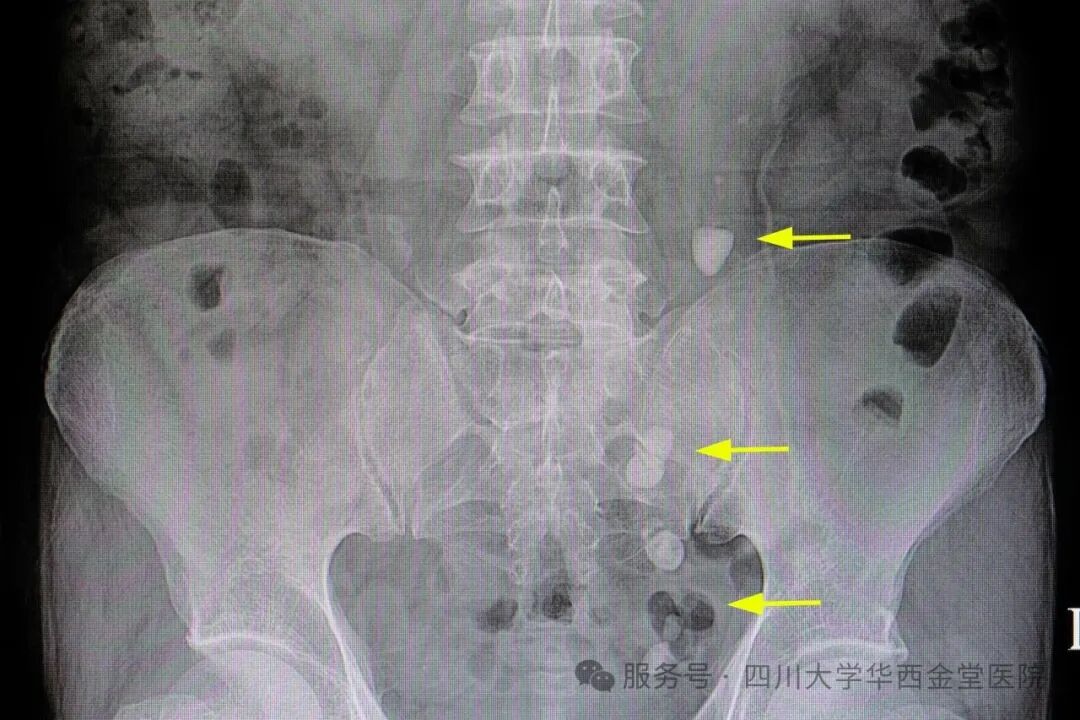

输尿管结石:小石头,大麻烦!【石狮体外碎石医院】

近年来,输尿管结石的发病率日益增加,给患者带来严重的困扰,尤其输尿管结石梗阻会引起剧烈的肾绞痛,发作起来不仅疼痛难忍,还会引起肾积水、尿路感染、甚至发生肾功能衰竭、尿源性脓毒血症、感染性休克、癌变等。今天我们就来认识一下输尿管结石治疗方法以及生活中可以怎样预防输尿管结石。